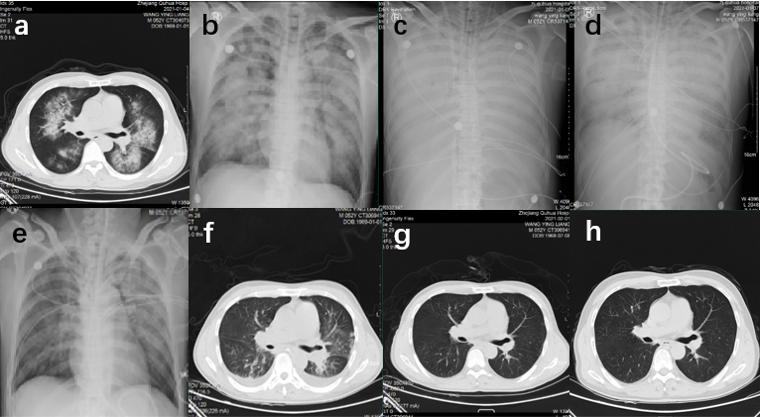

2 结果患者出院后每周复诊,1个月后每月复诊,3个月后每3个月复诊。除最危重的1号病例需用拐杖辅助行走外,其他患者均顺利回归社会,完全具备生活自理能力和低-中强度劳动能力。中毒后患者胸部CT或X线摄片呈两肺广泛性渗出,24 h内渗出至实变。中毒后3~5 d胸部X线摄片提示渗出开始吸收,2~4周胸部CT渗出完全吸收,其中2例患者残留少量条索纤维化病变,肺功能均恢复正常。中毒后4个月复查胸部CT病灶完全吸收。

以2号病例(见图 1)为例,患者中毒后6 h胸部CT呈双肺广泛渗出、磨玻璃样变;13 h胸部X线摄片呈双肺广泛实变,典型的“大白肺”;1 d后仍为双肺实变;3 d后双肺实变开始减轻;7 d后肺部渗出明显减少,部分磨玻璃样变;12 d后CT提示双肺呈少量磨玻璃样变;中毒29 d胸部CT仅余胸膜下少量条索纤维化病变;中毒后127 d复查CT条索纤维化病变也完全吸收。

| A:中毒后入院时胸部CT;B:中毒后行ECMO前胸部X线摄片;C:中毒后2 d胸部X线摄片; D:中毒后4 d胸部X线摄片; E:中毒后8 d胸部X线摄片; F:中毒后13 d胸部CT; G:中毒后29 d胸部CT;H:中毒后127 d胸部CT 图 1 病例2中毒后胸部影像学的动态变化 Fig 1 Dynamic changes of chest imaging after poisoning in case 2 |